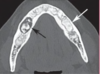

What is this radiographical finding?

Metastatic Carcinoma to Jaw Bones

C. Periapical image of a metastatic lesion of breast carcinoma; note the irregular widening of the periodontal membrane spaces and patchy sclerotic bone reaction, especially around the roots of the molars